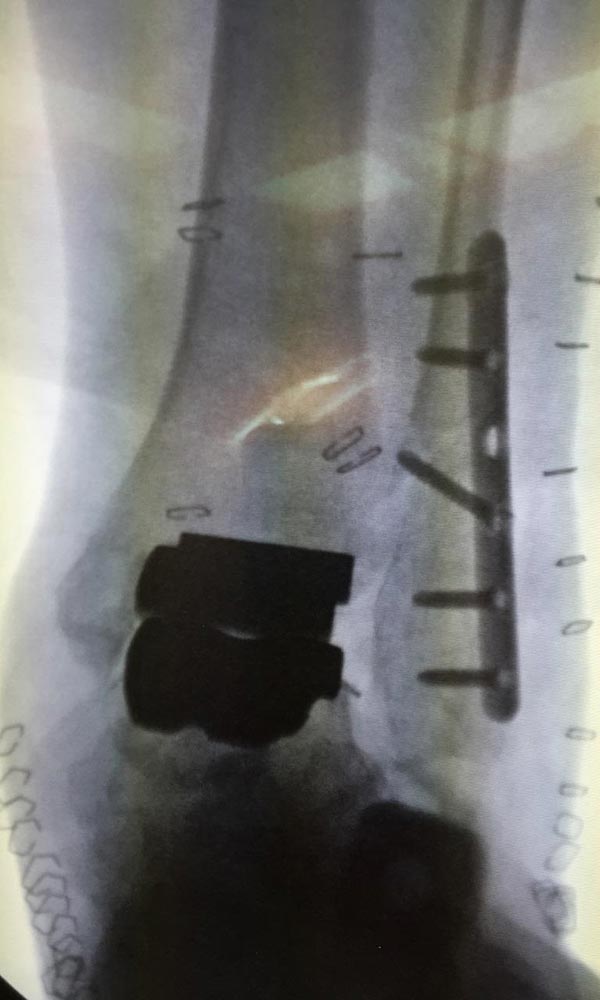

"Surgical misadventure" by another surgeon about 8 years ago. The wrong fixation was used for a flatfoot repair, & the deformity was not corrected. Patient came in with severe foot & ankle pain, with no arch at all. She was unable to play with her grandchild because the pain was so bad, & because she felt unsteady. The old hardware was removed, a lateral calcaneal lengthening osteotomy was performed along with a medial column/1st ray realignment. The ankle was painfully arthritic, & patient elected a total ankle replacement vs. an ankle fusion. She is now able to walk pain free & play with her grandchildren!